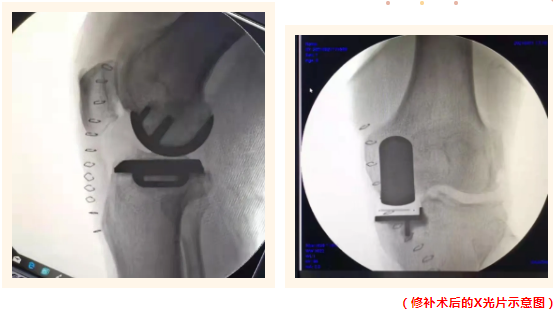

膝關(guān)節(jié)修補術(shù)(單髁置換)屬于保膝范疇,是一種精準(zhǔn)治療膝關(guān)節(jié)單間室磨損的微創(chuàng)新方法,類似于補牙的原理,把磨損的部位巧妙地以特殊材料修補起來,保留了沒有磨損的自然部分軟骨,完全保留了對膝關(guān)節(jié)穩(wěn)定起到重要作用的所有的韌帶系統(tǒng)。

誠德骨科醫(yī)院集團(tuán)已廣泛成熟開展膝關(guān)節(jié)單髁置換手術(shù)這項有著優(yōu)異效果的醫(yī)學(xué)技術(shù)。與全膝關(guān)節(jié)置換術(shù)比較,單髁置換手術(shù)時間短、創(chuàng)傷小、出血少、保留自身骨量和韌帶、術(shù)后病人感受好,功能恢復(fù)快,關(guān)節(jié)活動不受限制,手術(shù)并發(fā)癥少,牛津活動平臺單髁,術(shù)后關(guān)節(jié)功能更接近人體生理狀態(tài),成為了膝關(guān)節(jié)骨性疾病病人的福音。